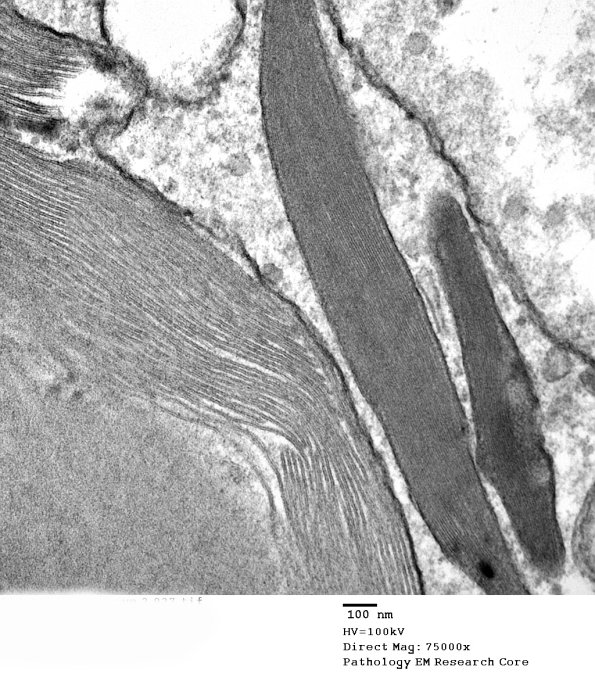

The smaller Pi granule has a typical periodicity but the large inclusion has an unusual appearance and increased periodicity. (Electron micrograph)